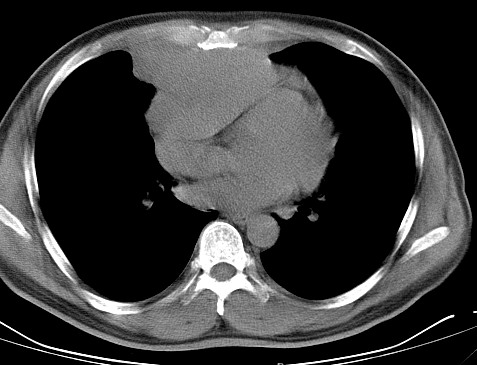

男   40   反复腹痛入院行彩超检查示胸骨右缘4、5肋间不均质回声团

淋巴瘤:前纵隔可见多组肿大的淋巴结,部分融合,有液化坏死

莲蓬籽征  考虑淋巴瘤